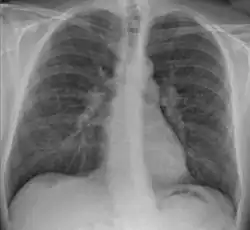

-

Hilar adenopathy especially on the person's left (lateral CXR) -